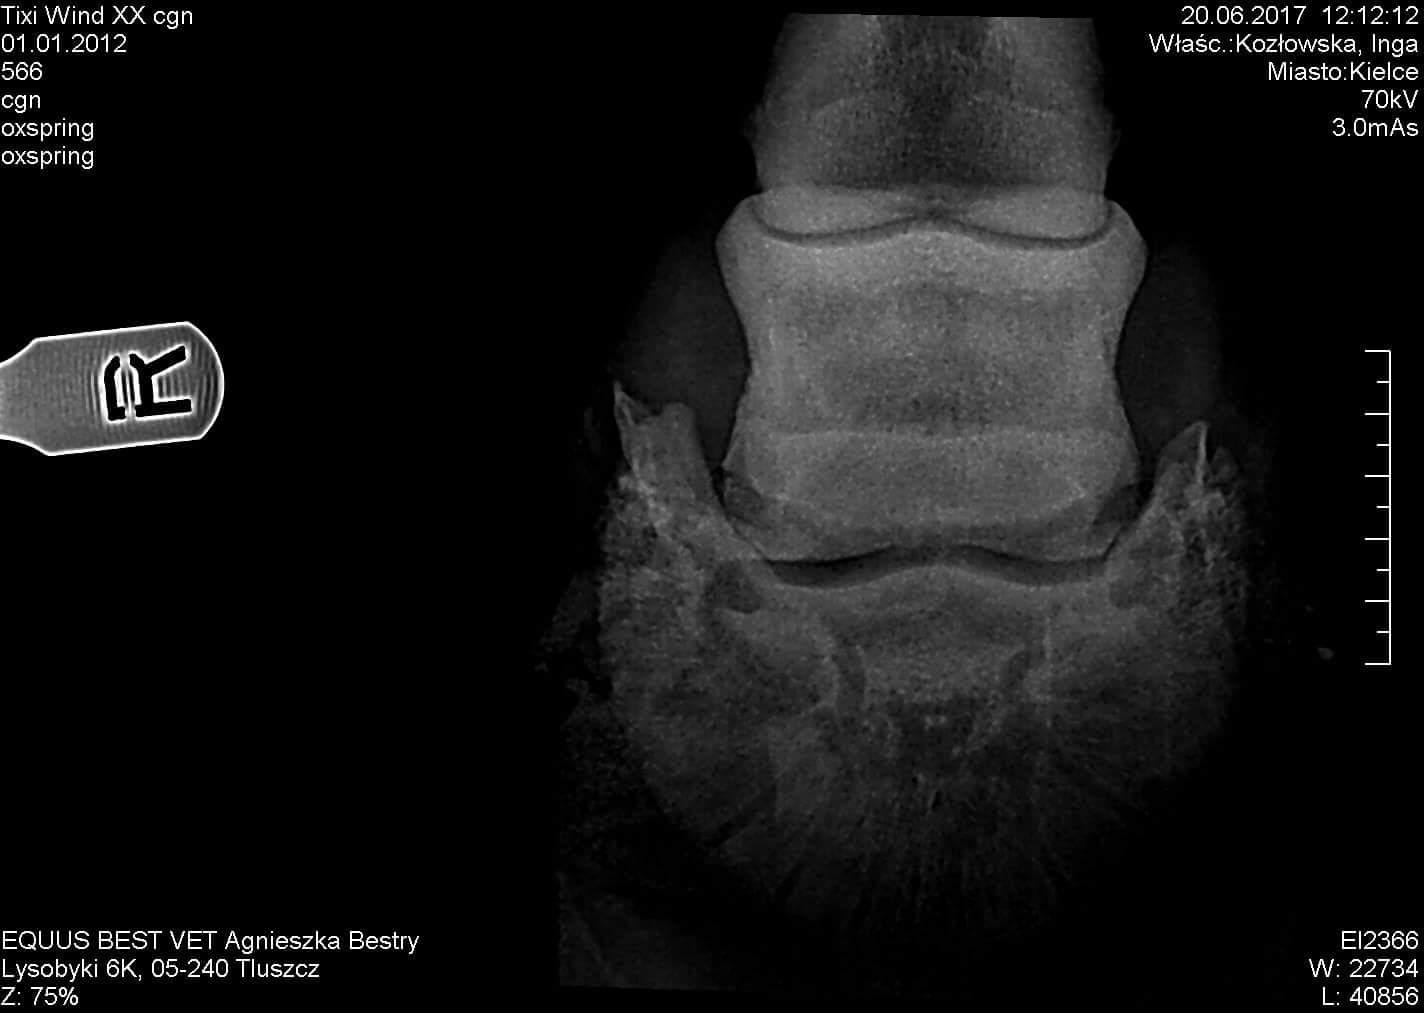

My 9 yo mare was diagnosed with navicular syndrome. Could you please take a look at those x-rays to See if you can also tell its navicular syndrome or maybe something else? Just want to double check while we are waiting for another vet. Thank you so much

Hi there. To me it looks like sidebone. Here is the link to an article about sidebone in horses: http://www.clydevetgroup.co.uk/equine/newsletters/dec07.htm I think the navicular bone itself looks OK to me however, when I zoom into the photo some detail is lost and it makes it difficult to evaluate. Also, you don't have all the x-ray views here for me to throughly evaluate the navicular bone. There should be a lateral view. That being said, I see no cones, lollipops or cysts on the navicular bone which are all things you can see with that disease process. Without knowing much of the history and what tests your vet has or has not done - just going on these x-rays - I would say the problem is sidebone. I hope this helps. Best wishes to you.